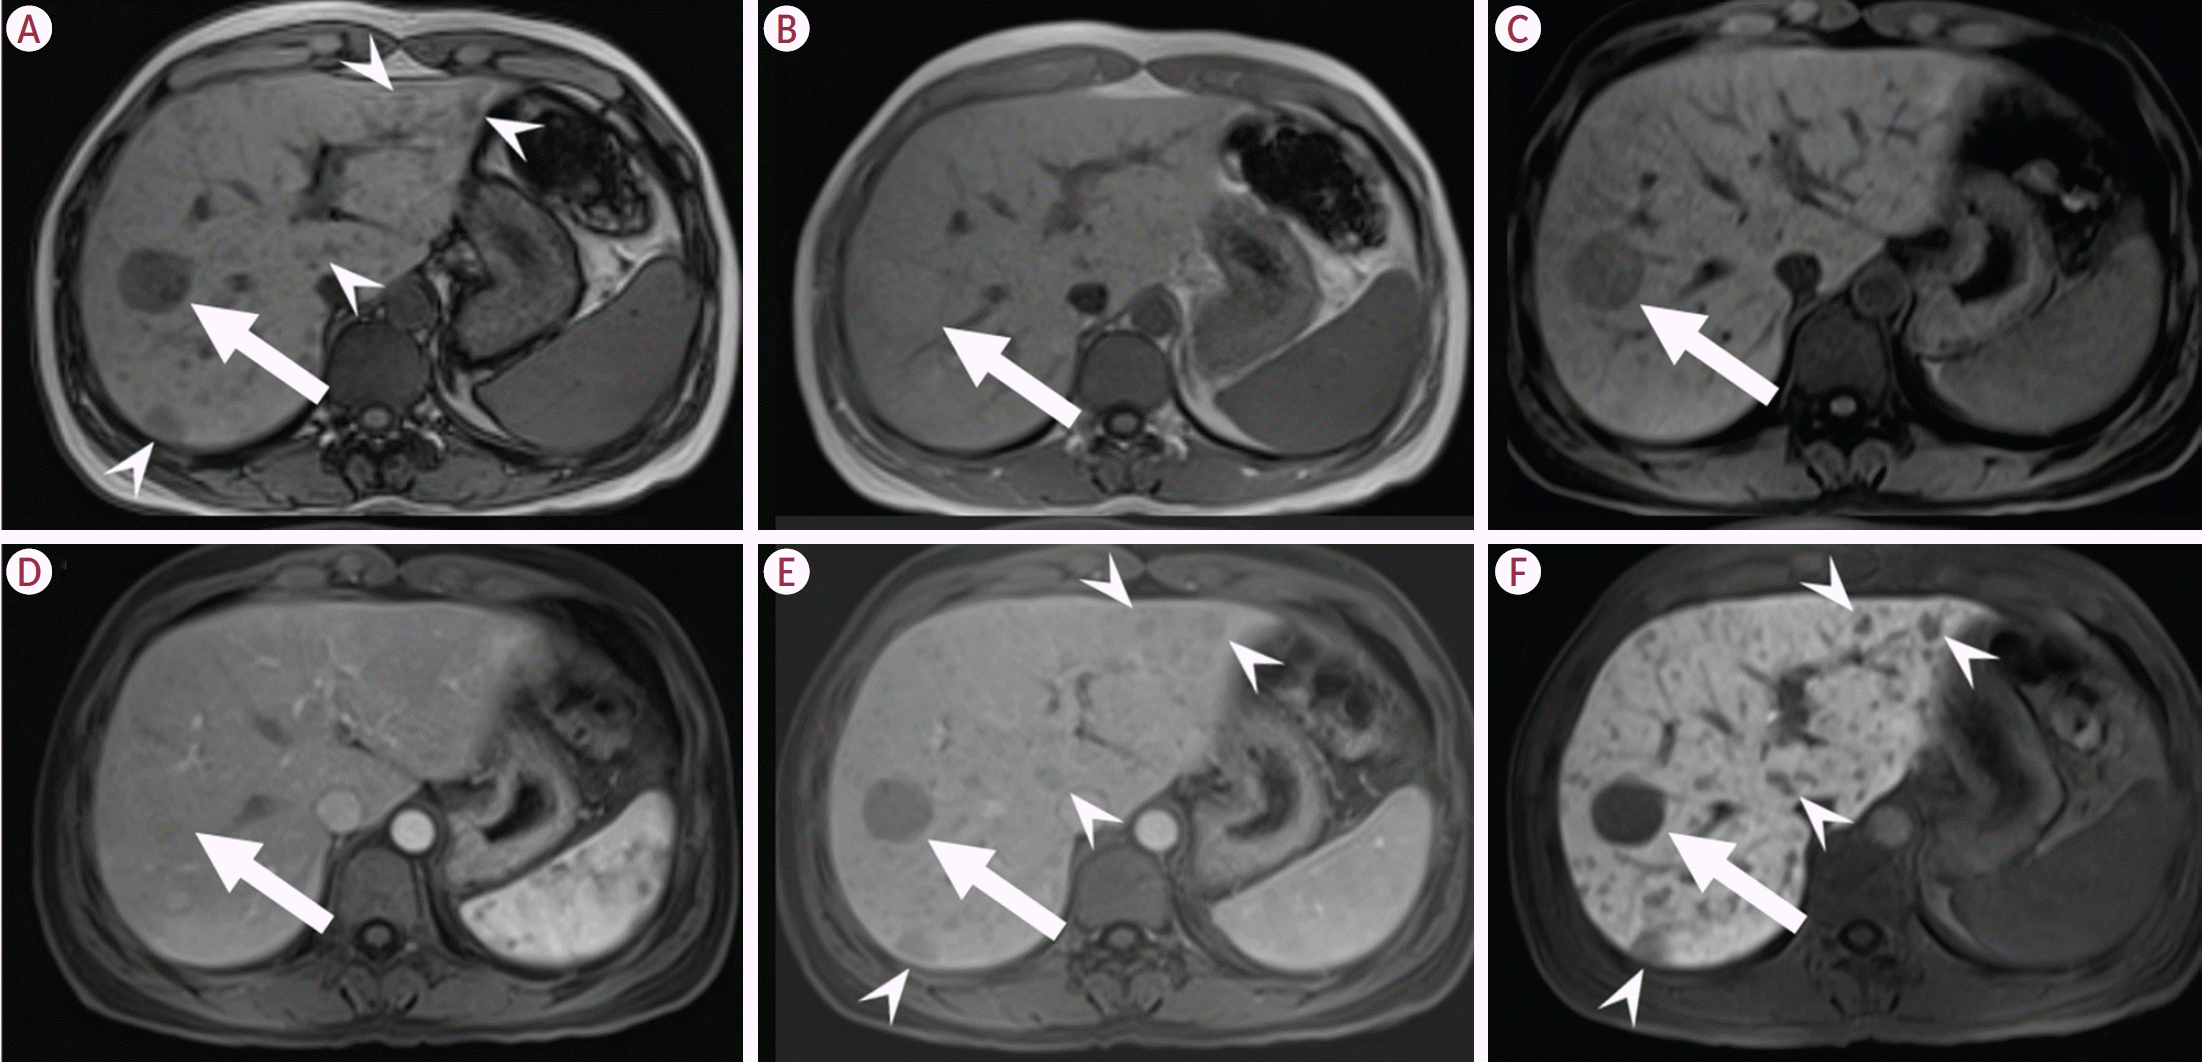

30. Laumonier H, Bioulac-Sage P, Laurent C, Zucman-Rossi J, Balabaud C, Trillaud H. Hepatocellular adenomas: magnetic resonance imaging features as a function of molecular pathological classification. Hepatology. 2008; 48:808–818.

31. van Aalten SM, Thomeer MG, Terkivatan T, Dwarkasing RS, Verheij J, de Man RA, et al. Hepatocellular adenomas: correlation of MR imaging findings with pathologic subtype classification. Radiology. 2011; 261:172–181.

32. Ba-Ssalamah A, Antunes C, Feier D, Bastati N, Hodge JC, Stift J, et al. Morphologic and molecular features of hepatocellular adenoma with gadoxetic acid-enhanced MR imaging. Radiology. 2015; 277:104–113.

33. Bise S, Frulio N, Hocquelet A, Alberti N, Blanc JF, Laurent C, et al. New MRI features improve subtype classification of hepatocellular adenoma. Eur Radiol. 2019; 29:2436–2447.

34. Lee SY, Kingham TP, LaGratta MD, Jessurun J, Cherqui D, Jarnagin WR, et al. PET-avid hepatocellular adenomas: incidental findings associated with HNF1-α mutated lesions. HPB (Oxford). 2016; 18:41–48.

40. Glockner JF, Lee CU, Mounajjed T. Inflammatory hepatic adenomas: characterization with hepatobiliary MRI contrast agents. Magn Reson Imaging. 2018; 47:103–110.

41. Agarwal S, Fuentes-Orrego JM, Arnason T, Misdraji J, Jhaveri KS, Harisinghani M, et al. Inflammatory hepatocellular adenomas can mimic focal nodular hyperplasia on gadoxetic acid-enhanced MRI. AJR Am J Roentgenol. 2014; 203:W408–W414.